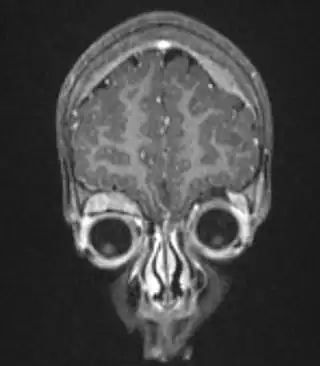

![]() Resonancia magnética de una niña de 2 años con neuroblastoma intracraneal. | ||